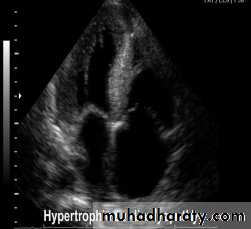

Hypertrophic cardiomyopathyThis is the most common form of cardiomyopathyGenetic disorder, usually with autosomal dominant transmission

The hypertrophy may be generalised or confined largely to the interventricular septum (asymmetric septal hypertrophy) or other regions (e.g. apical hypertrophic cardiomyopathy)

ECHO Echocardiography is diagnostic